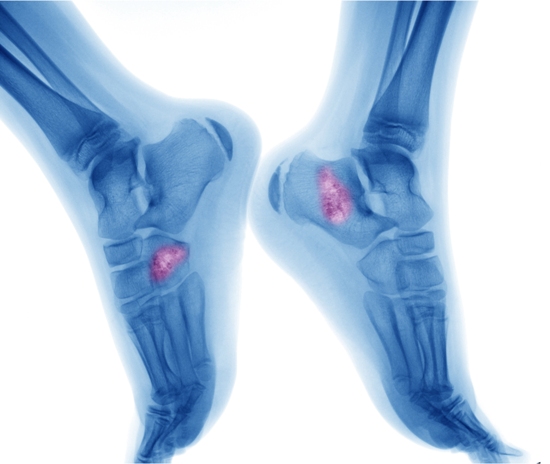

मायलोमा प्लाज्मा कोशिकाओं का कैंसर है जो रीढ़, सिर, पेल्विस और पसलियों में होता है। यह गंभीर किस्म का कैंसर है। इसके इलाज में प्राय: कीमोथेरेपी और स्टेम-सेल प्रत्यारोपण की पद्धति अपनाई जाती है। प्रोफेसर ग्राहम जैकसन ने कहा, ‘हमारे शोध से यह सामने आया है कि ऐसे मरीज जिनमें हाल ही में इस कैंसर की पहचान हुई हो, उन्हें स्टेम- सेल प्रत्यारोपण से पहले यह दवा देनी चाहिए।’ यह दवा इलाज की प्रक्रिया के दौरान मरीजों की सेहत को बेहतर रखने में मददगार है।

बोन मैरो यानि अस्थि मज्जा मुख्य हड्डियों के बीच में एक मुलायम व स्पॉंजी टिशू है। इसमें रक्त बनाने वाली अपरिपक्व कोशिकाएं होती हैं जिन्हें स्टेम सेल्स कहते हैं। स्टेम सेल्स लाल रक्त कोशिकाओं (जो पूरे शरीर में ऑक्सीजन पहुंचाती है), सफेद कोशिकाएं (जो संक्रमण से लड़ती हैं) और प्लेटलेट्स( जो ब्लड क्लॉटिंग से मदद करती है) में विकसित होती हैं।

बोन मैरो कैंसर दो तरह का होता है प्राइमरी और सेकंडरी। इन्हें प्राथमिक और माध्यमिक बोन कैंसर के नाम से भी जाना जाता हैं। जब बोन मैरो कैंसर के सेल्स हड्डियों के बजाए अन्य भागों में मिलते हैं तो ये प्राथमिक बोन कैंसर की श्रेणी में आता है। प्राथमिक बोन कैंसर के भी कई रूप हैं जैसे- ल्यूकेमिया, लिम्फोंमस और मल्टी माइलोमा। जब बोन मैरो में असामान्य रूप से सफेद कोशिकाओं का उत्पाद होने लगता हैं।

मल्टीपल माइलोमा कैंसर तब विकसित होता है जब बोन मैरो में प्लाज्मा सेल्स की उत्पति होने लगती हैं। लिम्फोमा आमतौर पर लसिका प्रणाली को प्रभावित करता है लेकिन कुछ और स्थितियों में भी बोन मैरो प्रभावित हो सकते हैं। जैसे बुखार होना, वजन का कम होना, हड्डियों में दर्द होना, बिना कारण फ्रैक्चर होना, एनीमिया, शारीरिक कमजोरी होना, शरीर में सूजन आना, ठीक से पोषण ना लेना, अत्यधिक थकान होना, चक्कर आना, प्रतिरोधक क्षमता कमजोर होना सभी बोन मैरो कैंसर और बोन कैंसर के लक्षणों में से एक हैं।